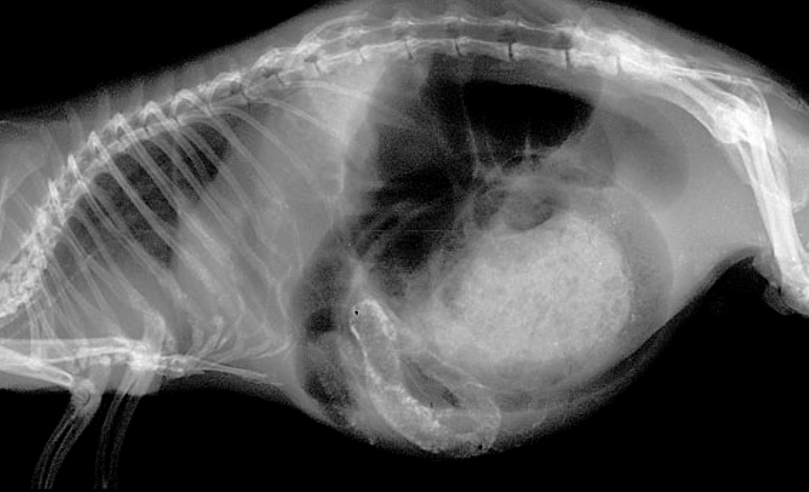

異所性石灰化とは正常骨以外の軟部組織へのカルシウムの非生理的な沈着で、モルモットでは頻繁にみられます〔Percy et al.2016〕。異所性石灰化は沈着部位により様々な障害をもたらしますが、モルモットでは、目、胃腸、肺、関節周囲などに起こりやすいです。石灰化はカルシウムとリンが高い状態が続くと発生し、餌の栄養の不均衡ならびに慢性腎不全〔Percy et al.2016〕が発生要因として考えられていますが、発生や病態に関してはよく分かってはいません。微細な異所性石灰化では無症状で、石灰化の大きさや広がりは様々で、多くは進行が遅いのが特徴です。X線検査で偶発的に発見できるものが多いです。餌の栄養の不均衡は栄養性二次性副甲状腺機能亢進症が発生要因として唱えられていますが、線維性骨異栄養症を起こしていない個体が多いため、実際の関与は不明です。